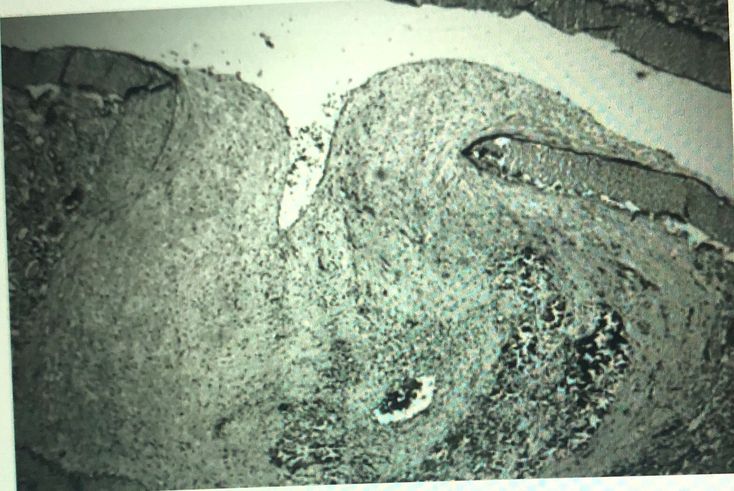

A 28-year-old African-American man presents to the physician with fever, weight loss, and abdominal pain. His blood pressure is 168/92mm Hg, his pulse is 83/min, and his respiratory rate is 18/min. On physical examination, there is palpable purpura on his lower extremities; a fundoscopic examination reveals fluffy, white spots on his retina. His past medical history is significant for a previous hepatitis B infection. An arterial biopsy is shown in the image. Which of the following is the most prominent morphologic feature of the affected arteries in this patient’s disease process? *  A- Caseating necrosis B- Eosinophilic infiltrate C- Fibrinoid necrosis D- Granulomatous infl ammation E- Langhans’ giant cells F- Onion skinning